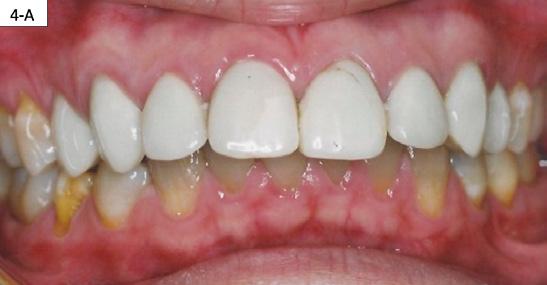

FIG. 4A: Pre-treatment, frontal view

FIG. 4B: Pre-treatment, right lateral view

FIG. 4C: Pre-treatment, left lateral view

FIG. 4D: Pre-treatment, maxilla, occlusal view

FIG. 4E: Mandible occlusal view

FIG. 4F: Pre-treatment, OB and OJ

Clinical dental appraisal revealed full Angle Class II molar and cuspid relationship. The arches were wide and there was a moderate crowding. The patient had 9.0 mm overjet and 6.0 mm overbite. However, the patient reported SDB symptoms, and he also presented with symptoms and signs of TM dysfunction (Figure 4A, B, C, D, E, F))

Clinical Micro-esthetic appraisal revealed signs of attrition and abrasion. Periodontal health was good, and the patient was devoid of tooth decay. However, there was a moderate number of restorations, generalized Tetracycline stain and failing porcelain veneers on the maxillary anterior teeth.